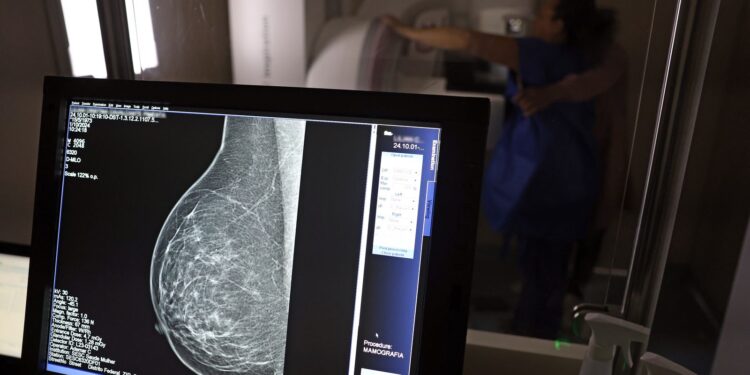

A partir de quantos anos se deve fazer a mamografia de rastreio, ou seja, como um exame de rotina, mesmo sem sintomas? Para autoridades públicas, como o Ministério da Saúde e o Instituto Nacional do Câncer (Inca), o ideal é que a mamografia seja feita a cada dois anos por todas as mulheres entre 50 e 69 anos. Algumas entidades médicas, como a Sociedade Brasileira de Mastologia (SBM), entretanto, recomendam exame anual a partir dos 40 anos.

Roberto Gil explica por que esses estudos consideram que os 50 anos são a idade certa para o início do rastreamento na população em geral: “Não estamos negando que mulheres abaixo de 50 anos tenham câncer de mama. Estamos falando que, abaixo dos 50 anos, acumulam-se outros problemas e o rastreamento populacional é menos eficiente. A mamografia é um exame de raio X, que vai ser mais efetivo na medida que a mama seja menos densa e que se tenha mais contraste na imagem, para não se confundir o parênquima normal com um nódulo. Então [antes dessa idade], aumenta muito mais a possibilidade de ter falsos positivos e ter que fazer mais exames. Posso fazer uma biópsia e ser mais difícil interpretar e levar a uma cirurgia desnecessária.”